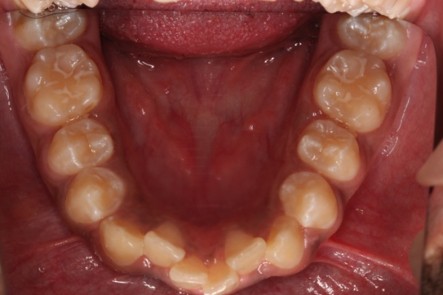

- Fillings

- Pulpotomy, pulpectomy

- Dental sealants